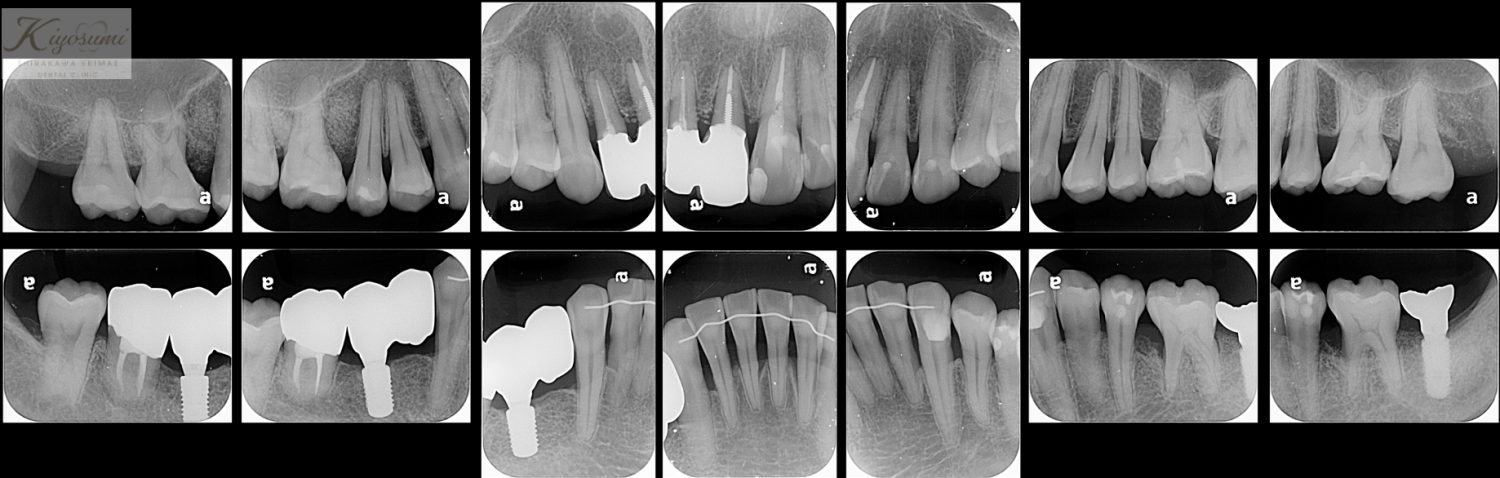

| 主訴 | 歯が揺れて噛めないので、噛めるようにして欲しい。 |

| 治療内容 | 基本的な歯周病治療、根の治療を実施し、歯の高さが足りない箇所は歯冠長延長術、保存が難しい歯は一部歯根分割抜去を行いました。欠損部はインプラントを用いず、ジルコニアブリッジで仕上げています。 |

| 想定されたリスク | ※残存している歯の本数が少ないため、残っている歯だけでブリッジを行うには長期予後が見込めない可能性があり、患者さんにご理解をいただいたうえで被せ物を行っています。 ※歯周病治療や根の治療をしても歯を残せない可能性がありました。 |